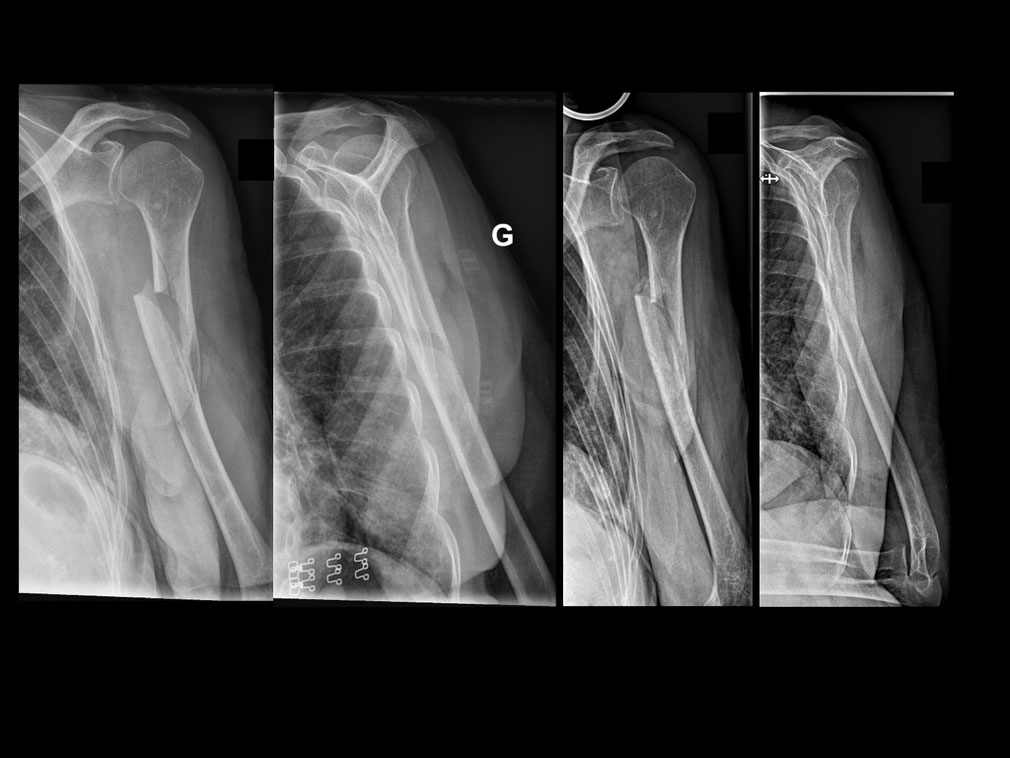

Clinical example of humerus fracture healing. Download Scientific Diagram

Clinical example of humerus fracture healing. Download Scientific Diagram How Long Does It Take For A Midshaft Humerus Fracture To Heal It can takes weeks to months for a humeral fracture to heal, depending on the severity. These fractures normally take between 6 to 12 weeks to heal. Once the fracture begins to heal it is important to keep the shoulder moving. How should it be treated? How long does it take humerus fractures to heal? Surgery usually involves fixation of. How Long Does It Take For A Midshaft Humerus Fracture To Heal.